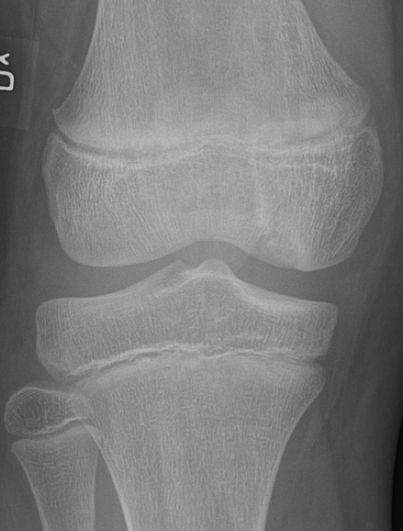

En broskbit med underliggande ben lossnar från metafys. Vanligast i mediala femurkondylen i ålder 10-19 år men kan hända i de flesta leder och även hos vuxna. [1, 2]

Osteokondrit i mediala femurkondylen hos 10-åring